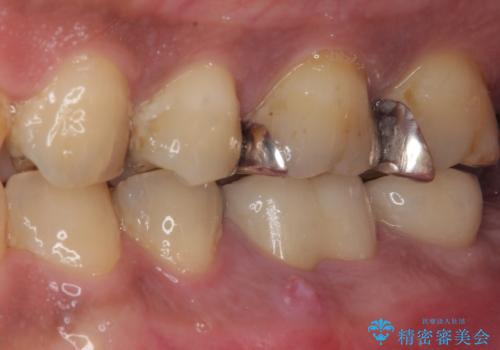

従来のインプラント治療ですと、抜歯をしてからその部分の骨が回復するまで数か月待機し、その後インプラント埋入、生着を待って土台の頭出し手術、仮歯の装着となるため、咬合回復するまでに半年かそれ以上の期間が必要となってしまいます。

咬合力の影響で歯が壊れてしまう方の場合、長期間欠損が続くと、連鎖するように他の歯が壊されてしまうリスクがあるため、抜歯即時インプラントにより、治療期間の短縮を図ることとしました。